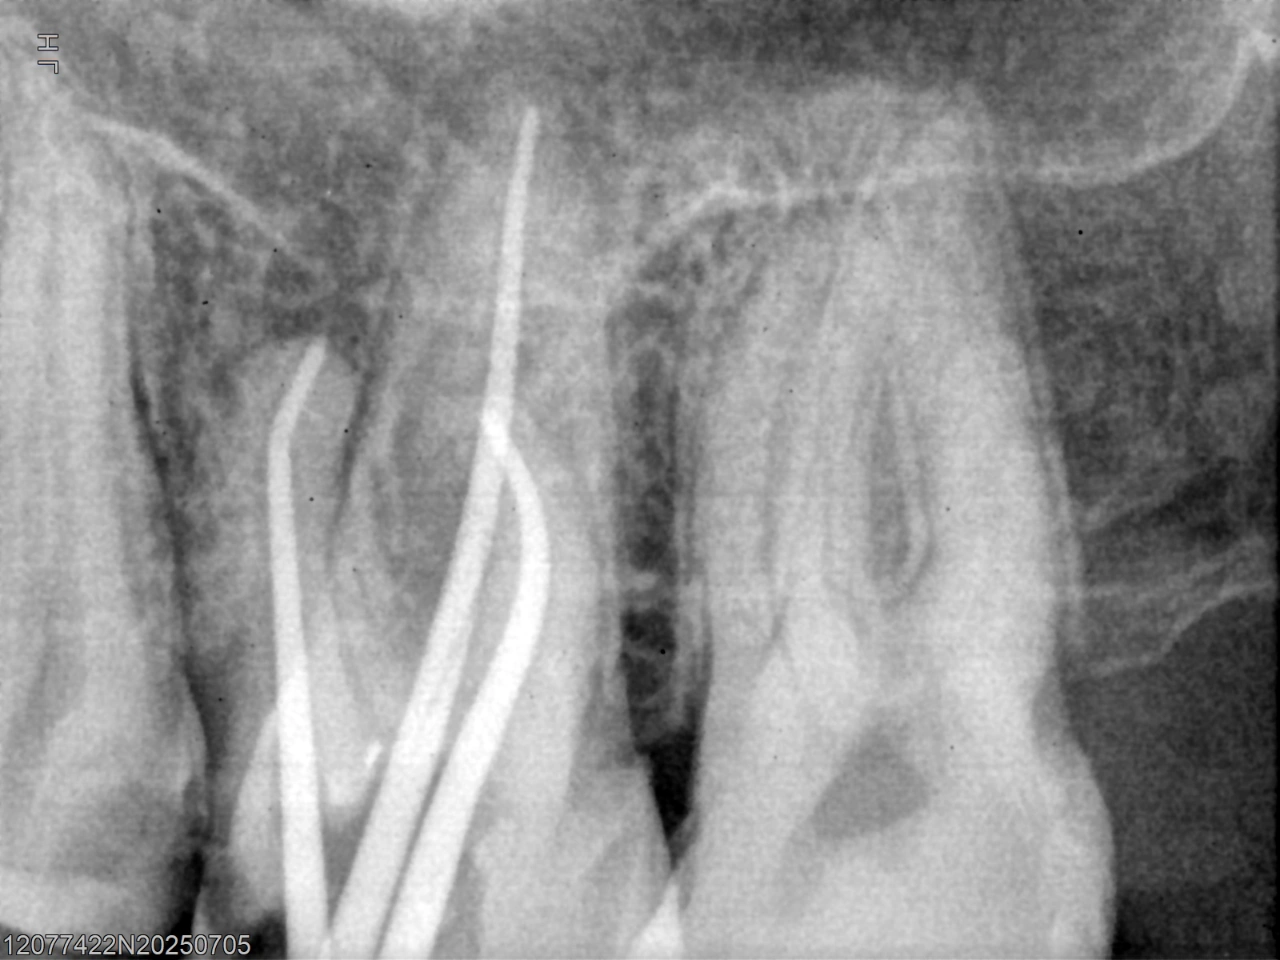

After removal of previous filling material.

Post-operative radiograph confirming complete obturation to the apex.

Outcome: Following adequate canal preparation, the canals were obturated to the correct working length, achieving a dense and well-sealed three-dimensional fill. Post-operative radiographs confirmed optimal obturation and improved apical sealing.